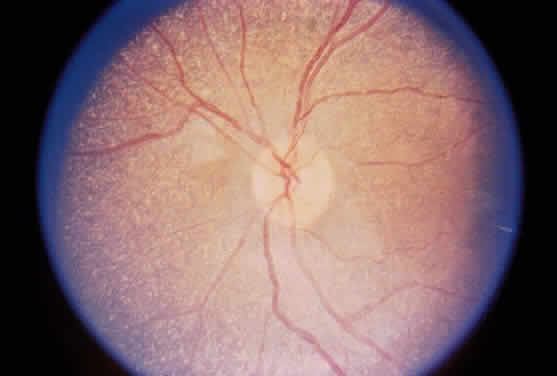

The essential fundus abnormality is a patchy depigmentation of the periphery and a finer “salt-and-pepper” disturbance at the posterior pole.72,79 Crystal deposition may also be seen (Fig. 7). Despite the extensive tissue infiltration of cystine crystals, there is no significant visual disturbance.